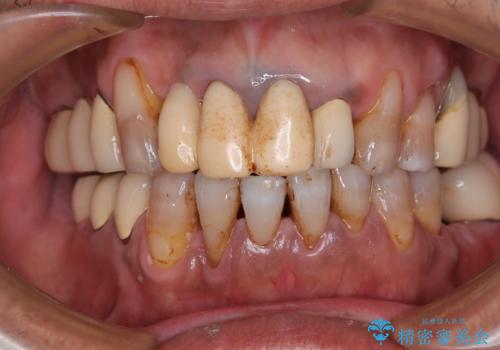

- 治療中の医院で装着した仮歯が汚れていて恥ずかしいとのことで来院された患者様です。

仮歯が不適合で歯肉が腫脹していたため、しっかりと調整した新しい仮歯にして腫れを改善した上で、オールセラミッククラウンにて補綴することとしました。

仮歯の隣の歯も詰め物の範囲が広く、仮歯をセラミックに置き換えても統一感のない口元となってしまうため、相談の結果、前歯6本をオールセラミッククラウンにて補綴治療を行うこととしました。